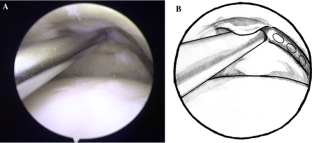

Fig. 1